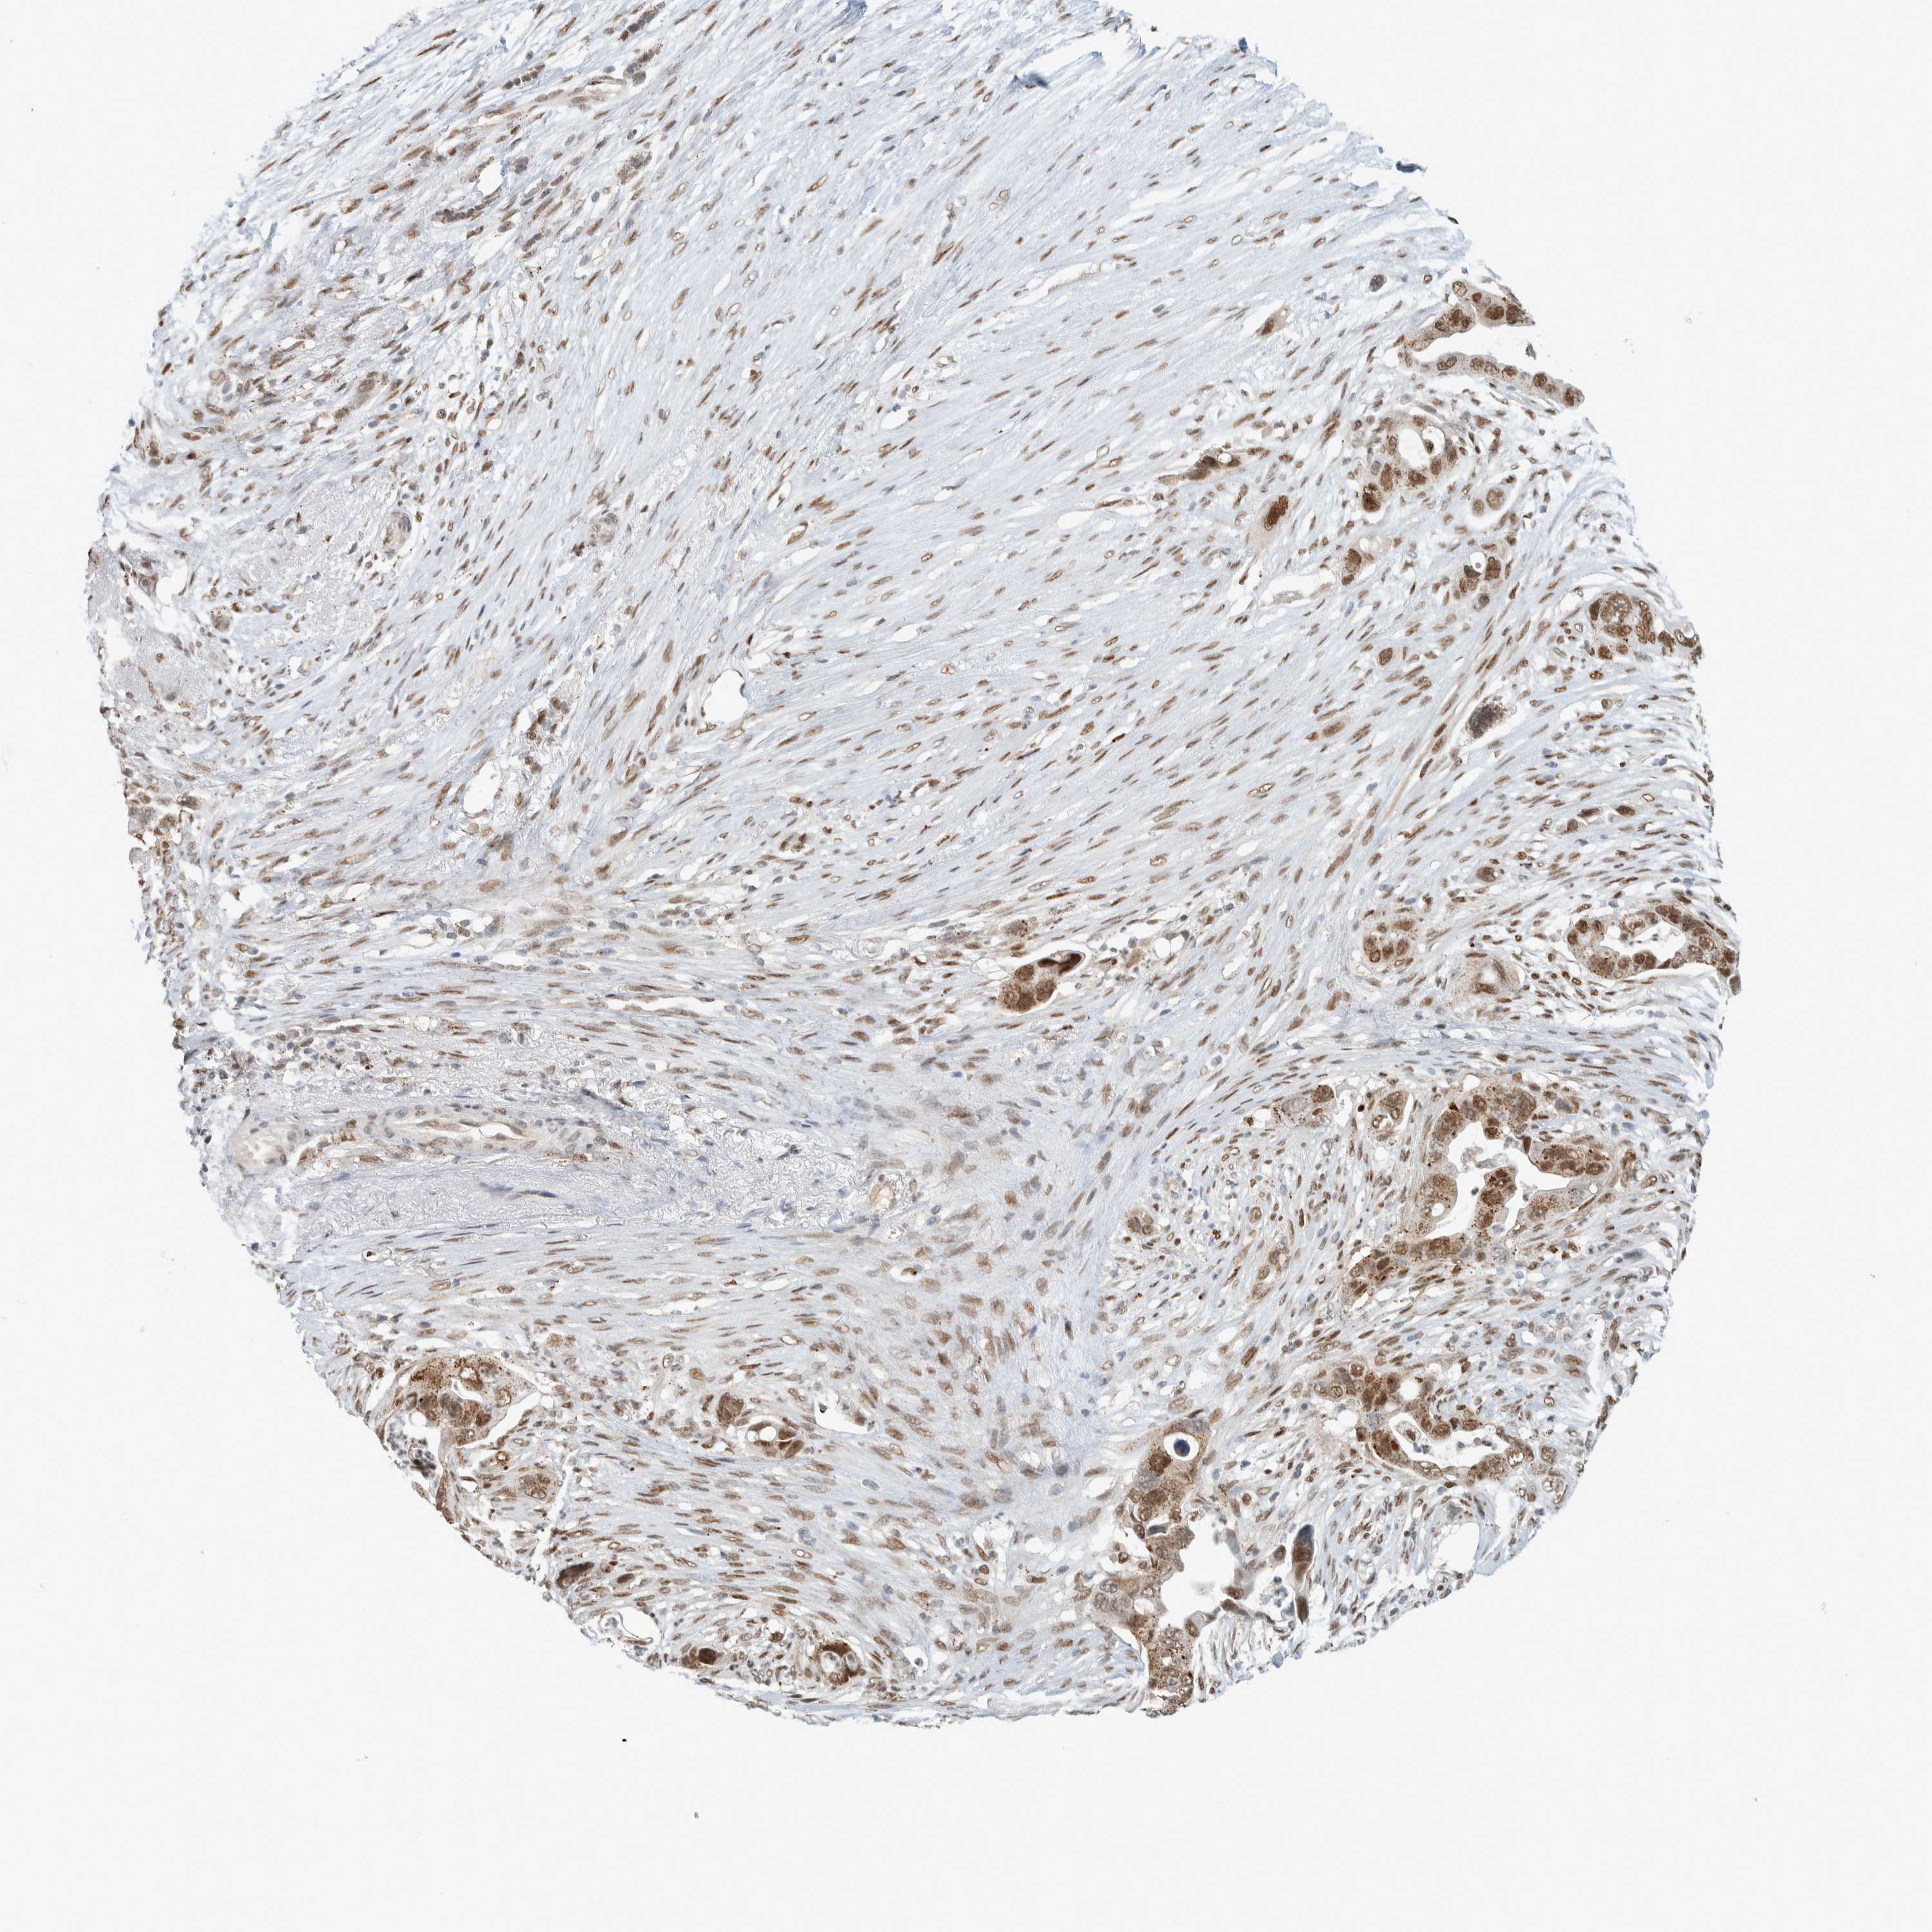

PANCREATIC CANCER - Protein expressioni

A mouse-over function shows sample information and annotation data. Click on an image to view it in a full screen mode. Samples can be filtered based on level of antibody staining by selecting one or several of the following categories: high, medium, low and not detected. The assay and annotation is described here.

Note that samples used for immunohistochemistry by the Human Protein Atlas do not correspond to samples in the TCGA dataset.

Antibody stainingi

Antibody staining in the annotated cell types in the current human tissue is reported as not detected, low, medium, or high, based on conventional immunohistochemistry profiling in selected tissues. This score is based on the combination of the staining intensity and fraction of stained cells.

Each image is clickable and will lead to virtual microscopy that enables deeper exploration of all samples and also displays staining intensity scores, fraction scores and subcellular localization as well as patient and tissue information for each sample.

Antibody HPA023881

Staining

High

Medium

Low

Not detected

Intensity

Strong

Moderate

Weak

Negative

Quantity

>75%

75%-25%

<25%

None

Location

Nuclear

Cytoplasmic/membranous

Cytoplasmic/membranous,nuclear

Adenocarcinoma, NOS